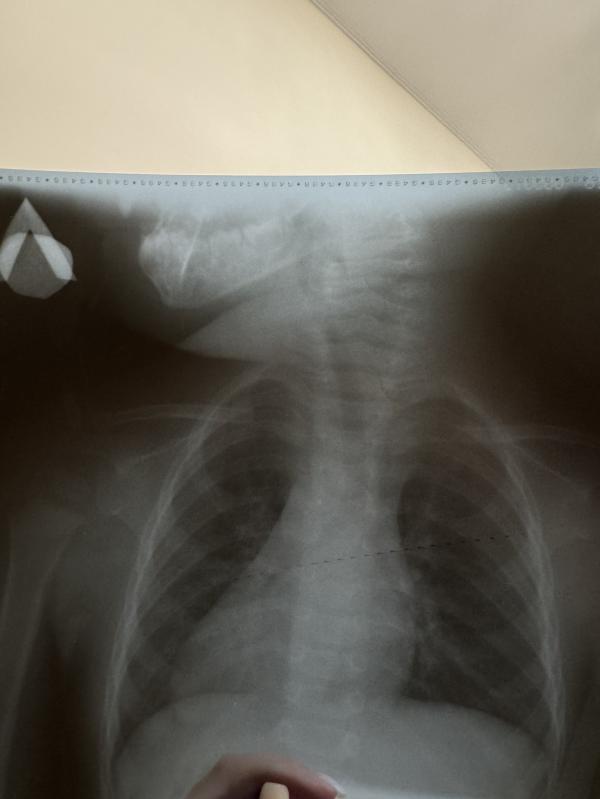

Меня так умиляет этот рентген снимок 😂

А все потому что, на нем видны зубки, которые еще не прорезались 🥺